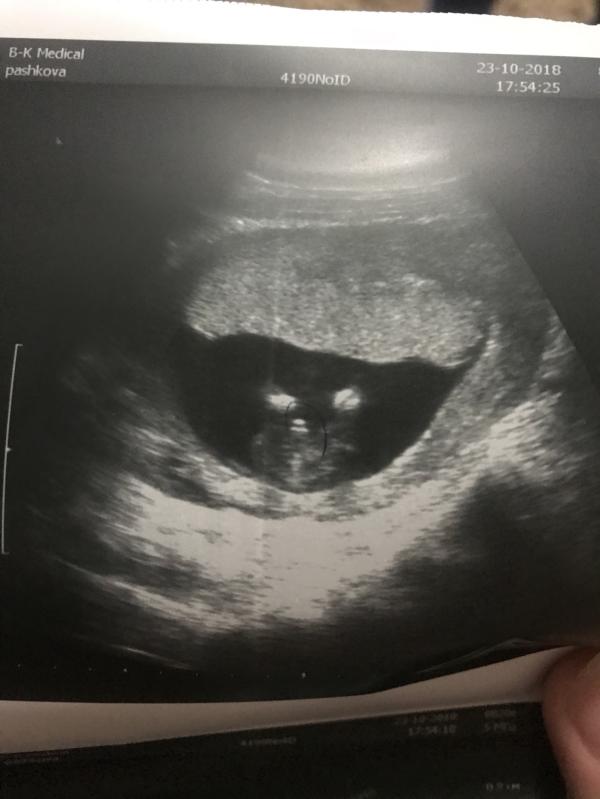

УЗИ в 15,3 недель! На фото прям 100% мальчик ? У кого девочки ? Там между ножек прям совсем совсем ничего не должно быть на таком сроке ? (Если есть, покидайте фото 🙏)

Всё три раза в 12-13 нед не ошибались, узисты были самые опытные, потом только подтверждали. Но шанс конечно ещё есть, сходите на 2 скрининг на 3D, там точно всё видно будет. Пока похоже это 👶 мальчик

15 недель это достаточный срок что бы хорошему специалисту не ошибиться с полом

На таком сроке половые органы выглядят практически одинаково. Пенис можно спутать с гипертрофированным клитором (он тоже торчит). Определяют по углу «торчания». Дождитесь 18 недель.